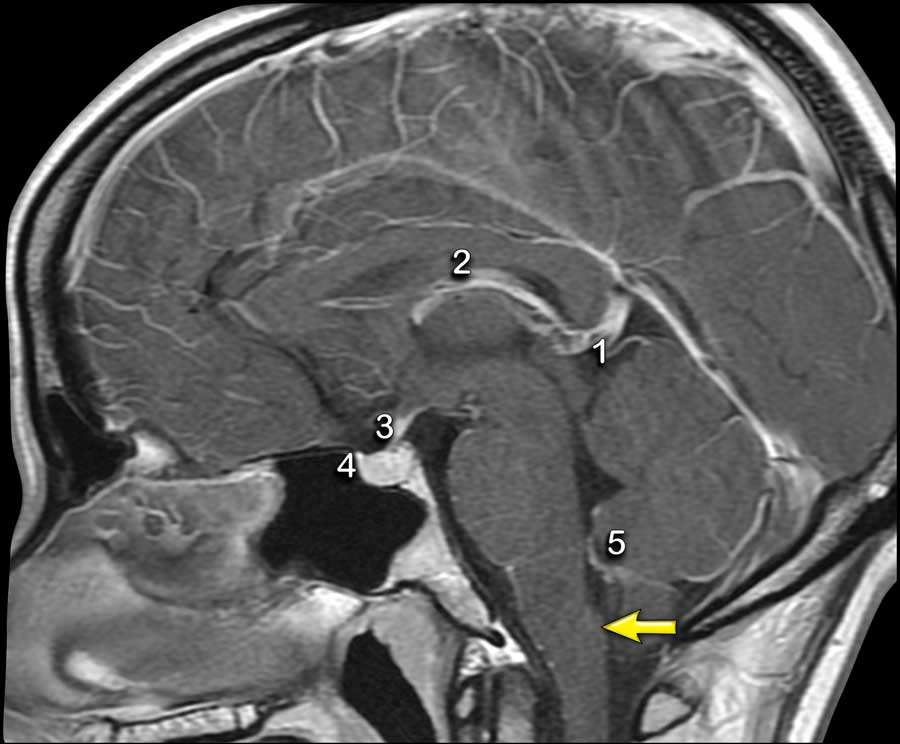

大脑中没有血脑屏障的结构或轴外结构将显示正常的增强。这些结构是硬脑膜、松果体 (1)、血管 (2)、垂体柄 (3) 和垂体 (4)、脉络丛 (5) 和延髓极后区(箭头)。延髓极后区含有丰富的有孔毛细血管,位于第四脑室底部的正下方。